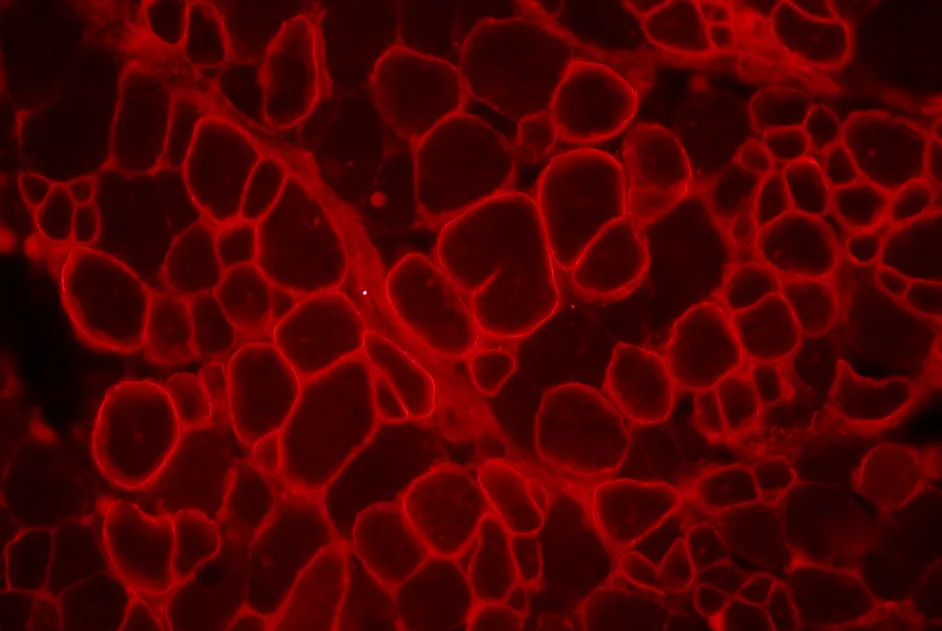

Myopathie de Duchenne : double thérapie génique chez la souris

Une stratégie de double thérapie génique apportant les gènes de micro-dystrophine et de la follistatine restaure la force de souris mdx âgées.